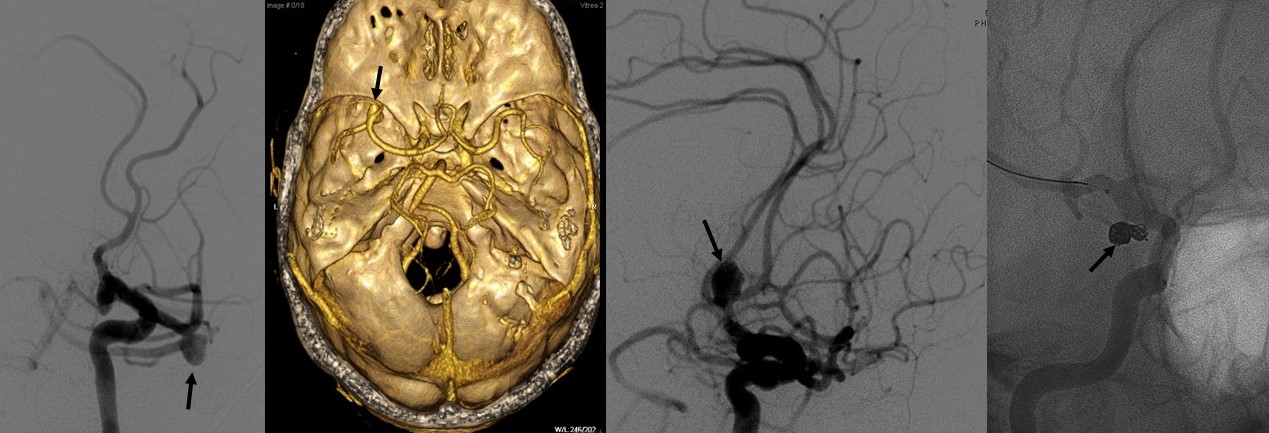

Tratamiento microquirúrgico de tumores cerebrales

Con una metodología de trabajo definida por nuestro firme compromiso con:

1. Seguridad del paciente

2. Planificación quirúrgica

3. Excelencia en la técnica microquirúrgica

4. Compromiso con el conocimiento científico